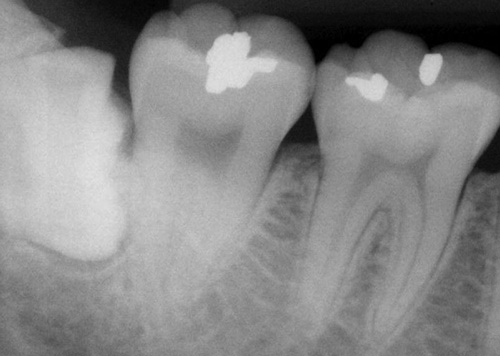

Orthodontic Treatment X-ray - After